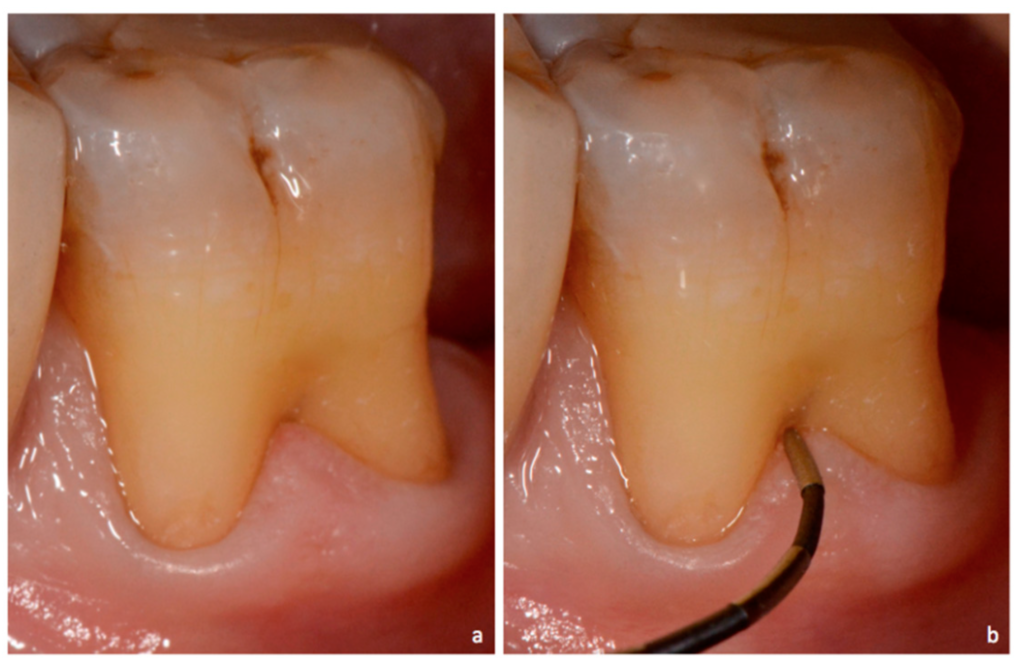

Le sondage parodontal est le gold standard clinique :

- Sonde parodontale graduée classique → pertes d’attache péri-dentaires

- Sonde de Nabers (courbe, millimétrée) → composante horizontale des lésions interradiculaires

- La composante verticale est estimée sur le cliché rétro-alvéolaire

Pourquoi c’est problématique : Une sonde droite ne permet pas d’explorer correctement la composante horizontale de la furcation, entraînant une sous-estimation systématique de la lésion.

Bonne pratique : Utiliser systématiquement la sonde de Nabers (courbe et millimétrée) pour quantifier la pénétration horizontale dans la furcation, en complément de la sonde droite pour les mesures verticales.

Point pédagogique : Une lésion de classe II peut être stabilisée par la thérapeutique étiologique seule si le patient adopte une hygiène rigoureuse. Le sondage de Nabers est ici l’outil diagnostique décisif — ni l’examen visuel ni l’OPG n’auraient permis ce diagnostic.

Quelle sonde utiliser pour explorer une atteinte de furcation et pourquoi ?

La sonde de Nabers est indispensable pour l’exploration des furcations. Sa forme courbe et millimétrée permet de longer le plafond de la furcation et de mesurer la pénétration horizontale, ce qu’une sonde droite ne peut pas faire correctement. Elle est utilisée en complément de la sonde parodontale classique pour les mesures verticales et les profondeurs de poche péri-dentaires.